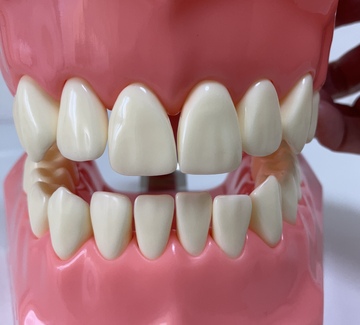

噛み合わせを模型上に再現

歯の矯正をする時などにするそうなんです。再現するとね。

舌が上顎にあると頭の位置がしっかりするわーと言ってもらえた

の。